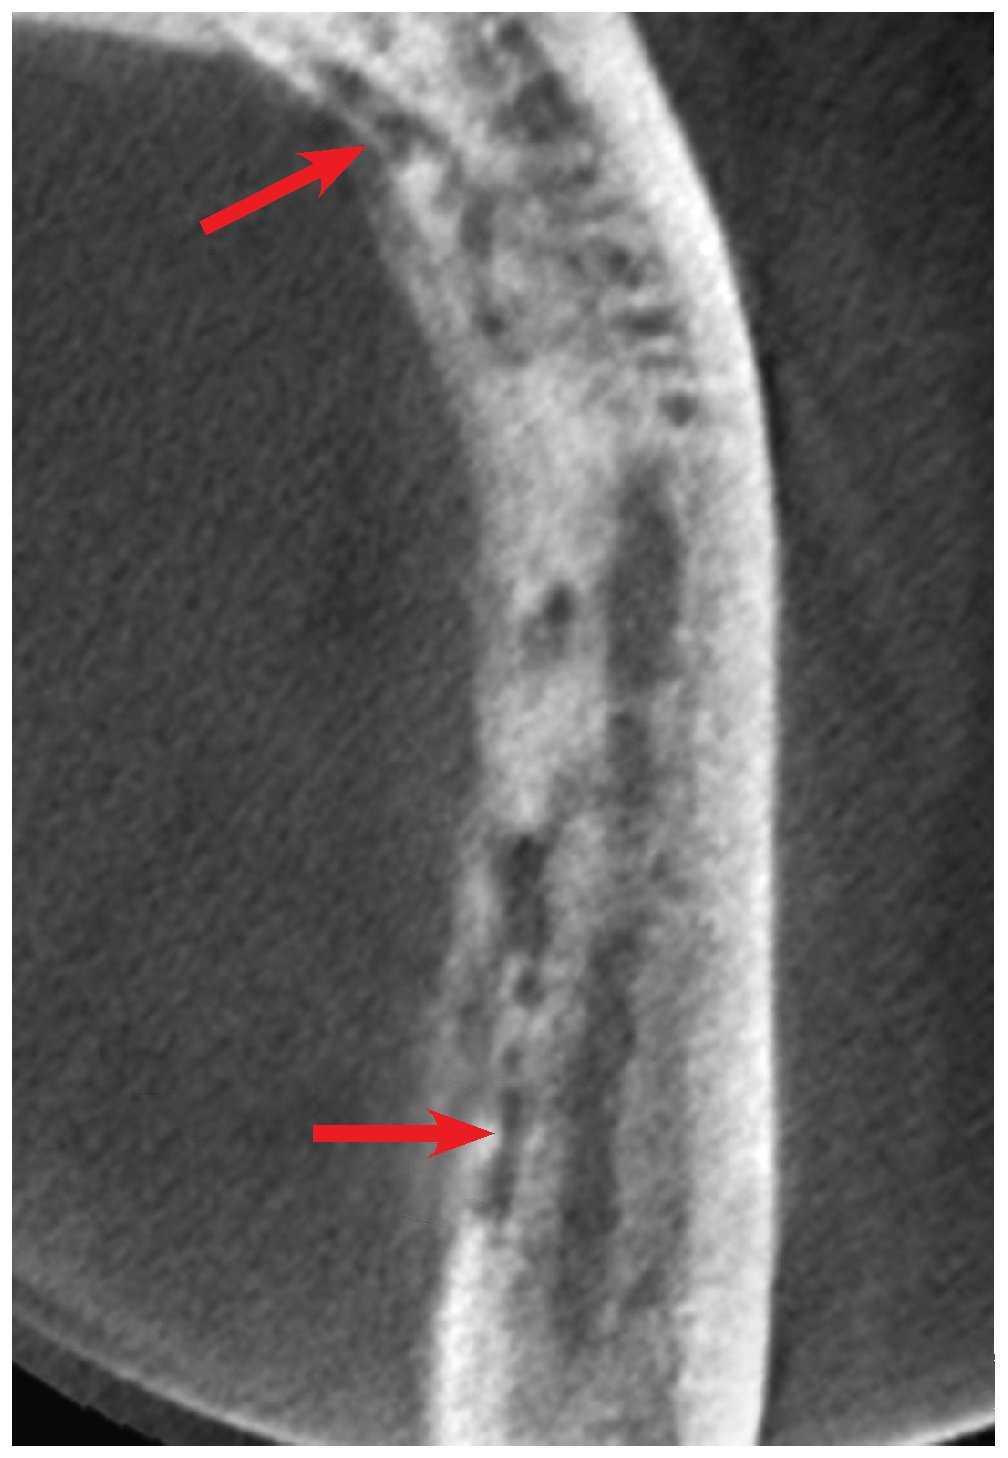

La tomografía volumétrica obtenida de forma complementaria (figs. 2 a 4) pone de manifiesto la magnitud de la alteración. Se identifican numerosas lesiones osteolíticas diseminadas en lingual del conducto dentario inferior izquierdo que se extienden hasta la región 31 (fig. 2). Esto provoca el desprendimiento parcial de estructuras óseas aisladas (fig. 3) que acaba finalmente en secuestros. Se aprecia además una reacción perióstica en el lado lingual (fig. 4). Los hallazgos descritos también concuerdan con un diagnóstico de osteomielitis supurada. Ahora bien, según la anamnesis, existe una gran probabilidad de que estén relacionados con la exodoncia practicada sobre una zona previamente afectada por el tratamiento con bifosfonatos.

Figura 4. Tomografía volumétrica digital dental, plano coronal/transversal.